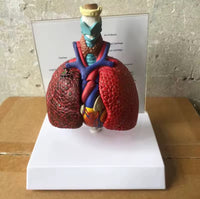

Modelo cardiopulmonar sistema respiratorio laringe

El modelo cardiopulmonar muestra Laringe humana, modelo pulmón cardiopulmonar, corazón, laringe, tráquea, nodos linfáticos, caja torácica médica